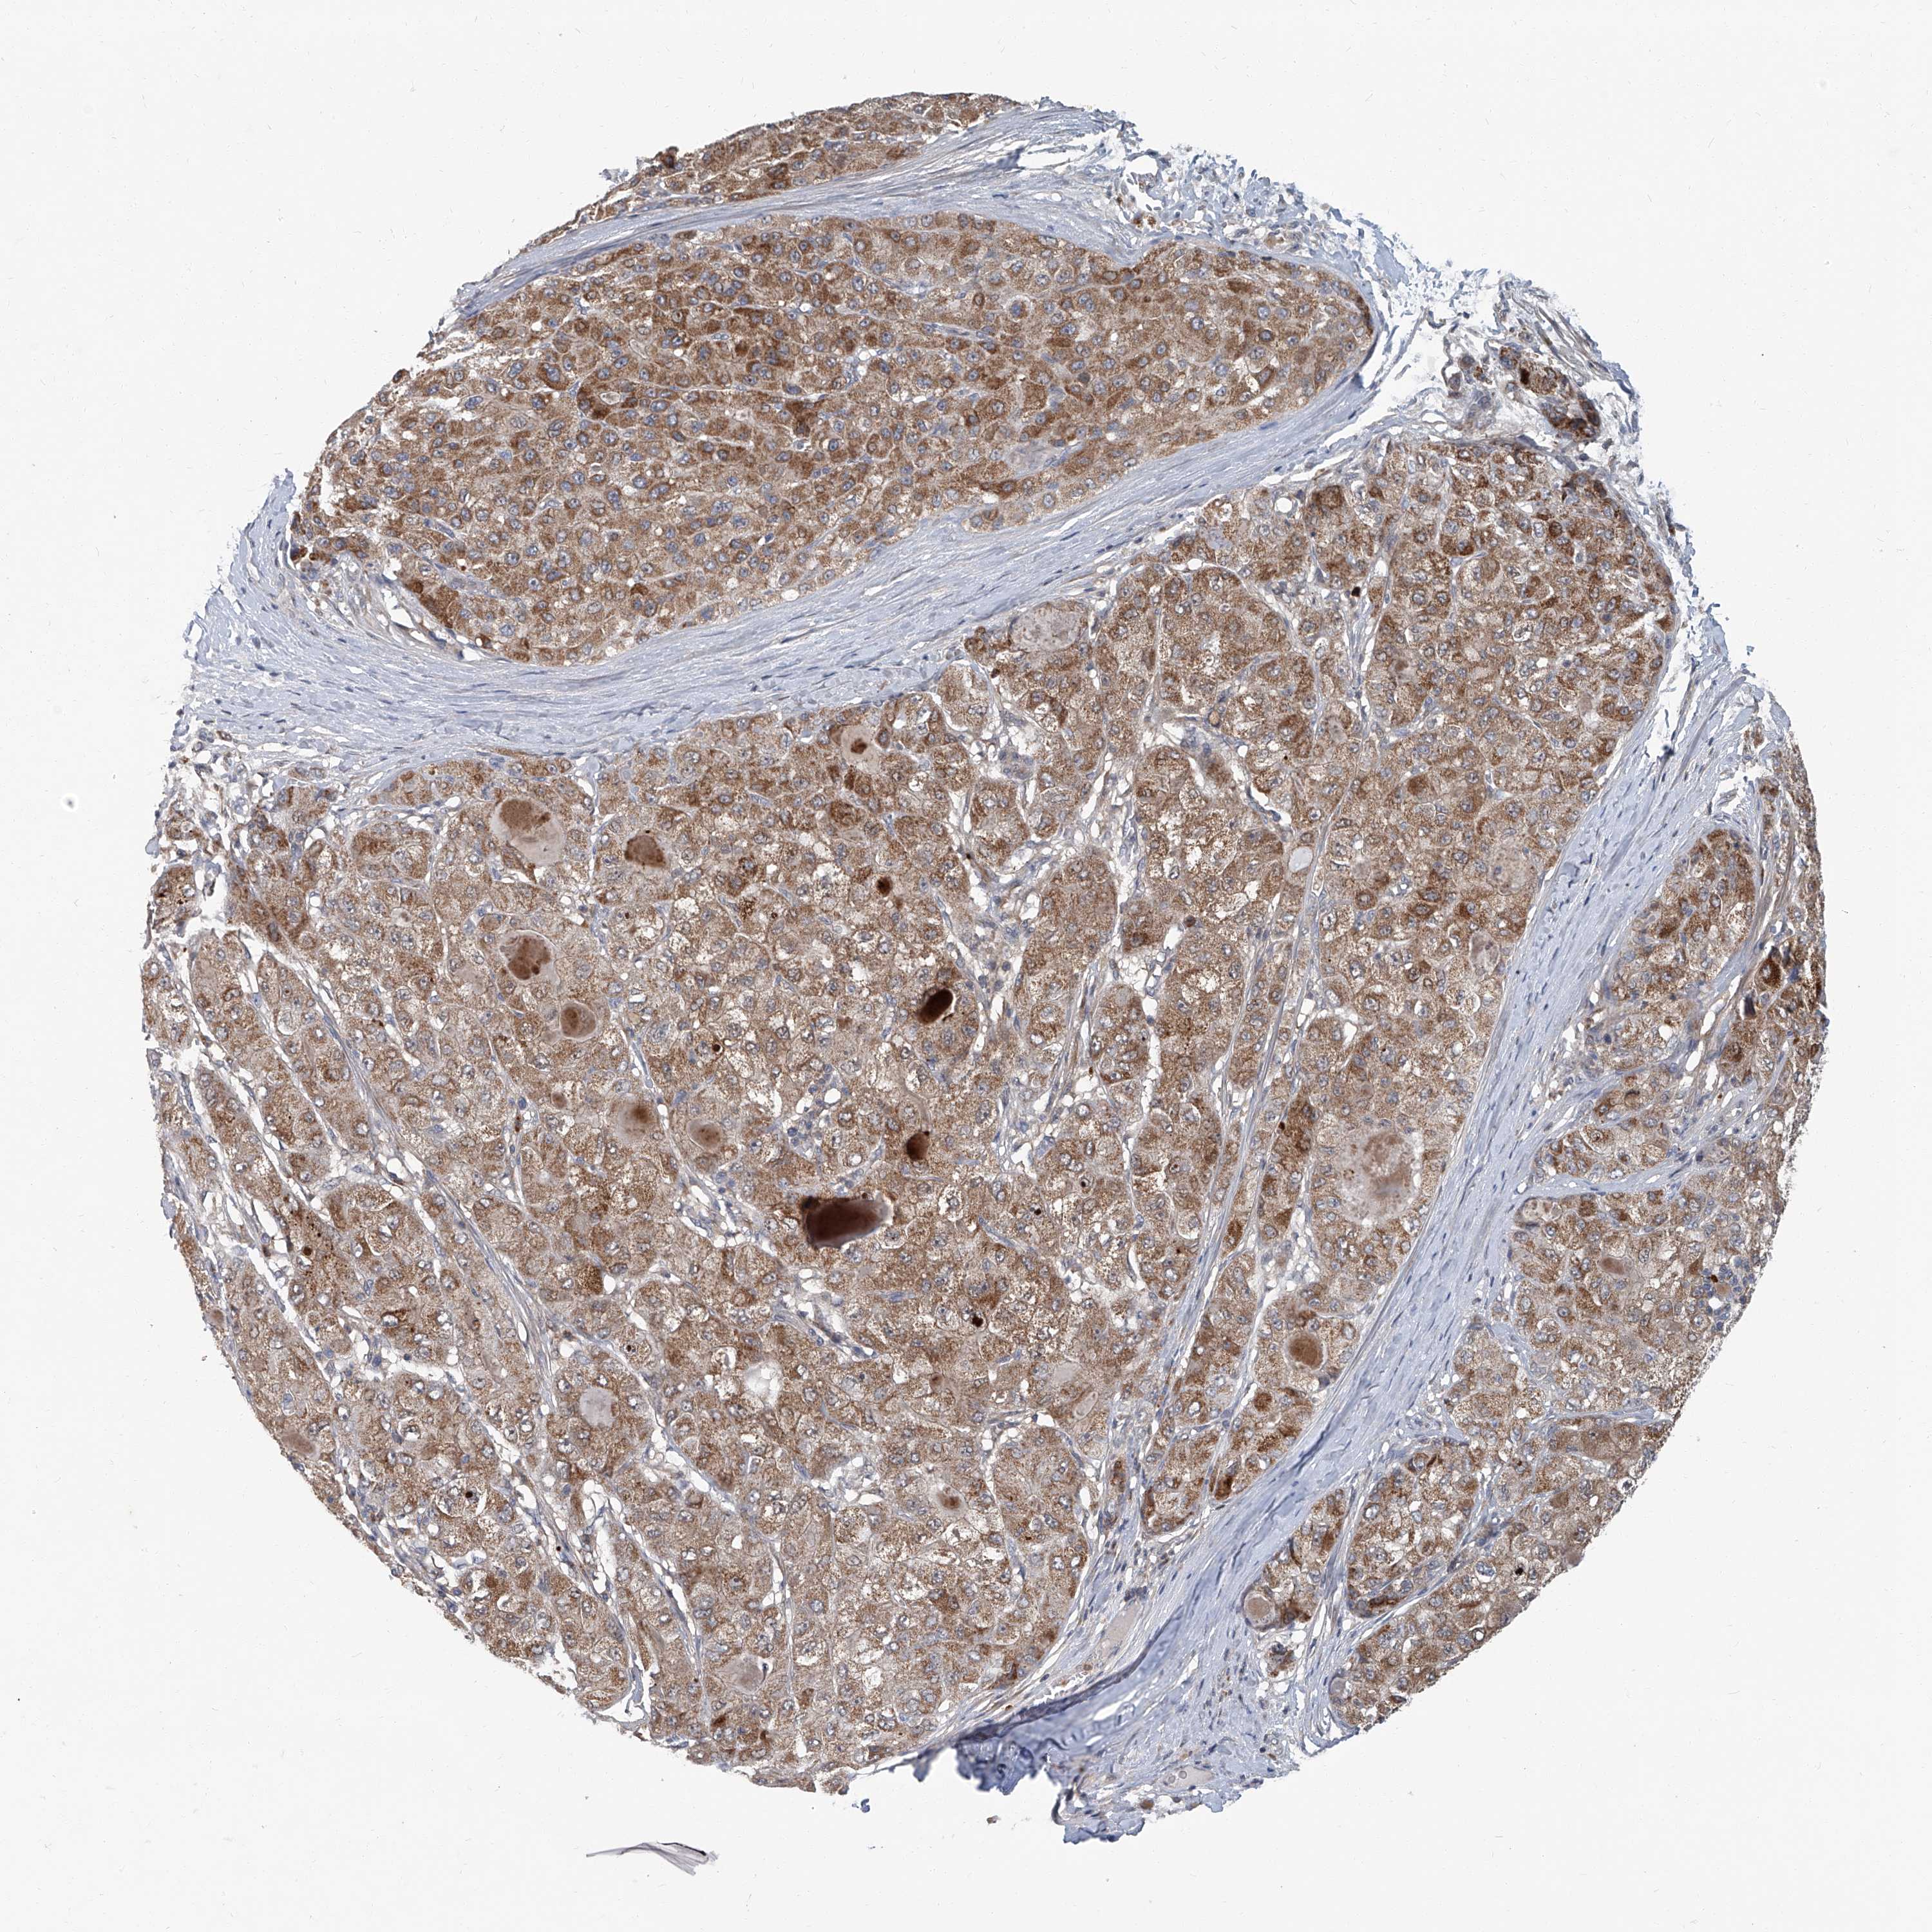

LIVER CANCER - Protein expressioni

A mouse-over function shows sample information and annotation data. Click on an image to view it in a full screen mode. Samples can be filtered based on level of antibody staining by selecting one or several of the following categories: high, medium, low and not detected. The assay and annotation is described here.

Note that samples used for immunohistochemistry by the Human Protein Atlas do not correspond to samples in the TCGA dataset.

Antibody stainingi

Antibody staining in the annotated cell types in the current human tissue is reported as not detected, low, medium, or high, based on conventional immunohistochemistry profiling in selected tissues. This score is based on the combination of the staining intensity and fraction of stained cells.

Each image is clickable and will lead to virtual microscopy that enables deeper exploration of all samples and also displays staining intensity scores, fraction scores and subcellular localization as well as patient and tissue information for each sample.

Antibody HPA030270

Antibody HPA030271

Antibody HPA030272

Staining

High

Medium

Low

Not detected

Intensity

Strong

Moderate

Weak

Negative

Quantity

>75%

75%-25%

<25%

None

Location

Nuclear

Cytoplasmic/membranous

Cytoplasmic/membranous,nuclear

Cholangiocarcinoma

Carcinoma, Hepatocellular, NOS